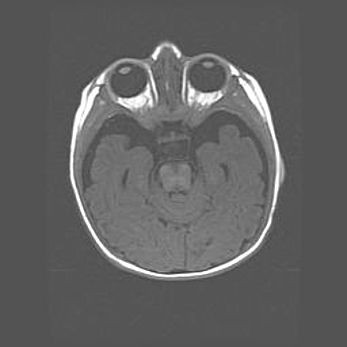

Церебральная ишемия II.

Возраст: 5 дней

Вес: 3400 г

Пол: женский

Окружность головы: 35 см

Срок гестации: 39 недель

Церебральная ишемия – это заболевание, характеризующееся недостаточностью (гипоксией) либо полным прекращением (аноксией) снабжения мозга кислородом по причине закупорки одного или нескольких сосудов. Это приводит к  что метаболическим расстройствам различной степени тяжести в тканях головного мозга, развитию коагуляционных некрозов и гибели нейронов.